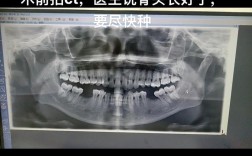

| 骨结合失败 | 骨量不足、手术创伤过大、过早负重 | 取出种植体,待骨愈合后重新种植或植骨后种植 | 术前完善CBCT评估骨量,术后遵医嘱避免过早负重 |